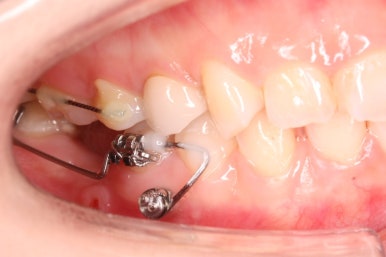

뼈의 상태 등에 따라 다를 수 잇지만 이번 경우는 5개월 뒤 임플란트가 완성이 되었습니다.

빈공간이 굉장히 자연스럽게 메워진 것을 볼 수 있죠.

부산부분교정을 하기 전과 후의 모습입니다.

부분교정으로 하였기 때문에 다른 치아의 변화는 전혀 없습니다. 또한 비교적 짧은 기간으로 원하는 목표를 달성했죠.

부분교정으로 매우 만족스러운 결과를 이끌어 냈습니다.